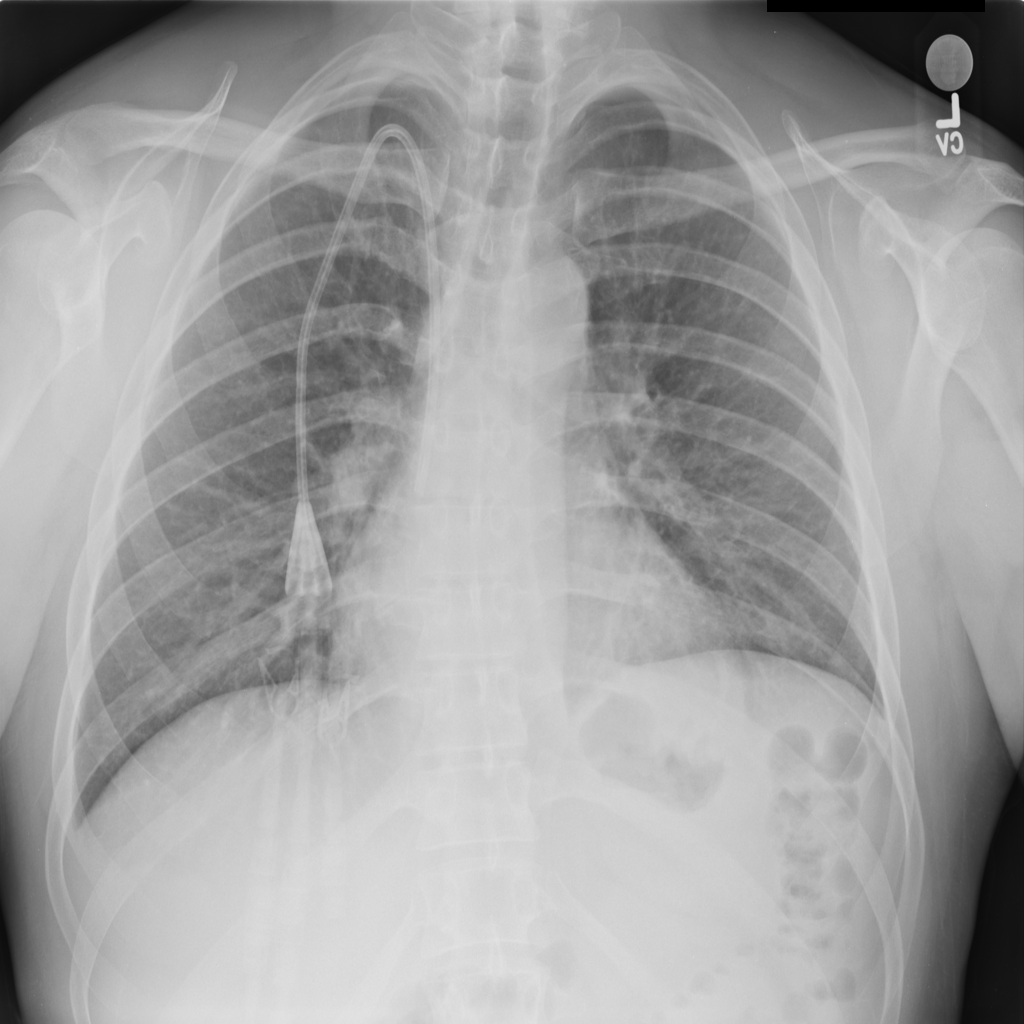

PAT-5B86 · IMG-009Edema

PAT-5B86 · IMG-009

PA